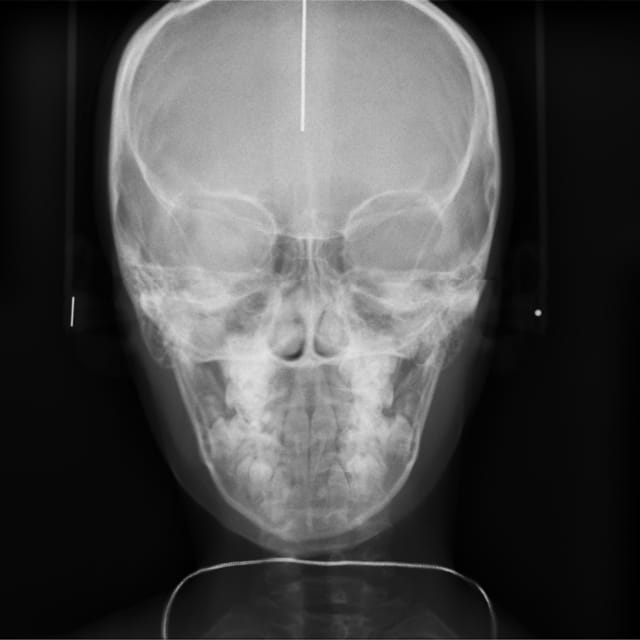

Radio t l  de face wliktb - Eugenol

Son ANB est de 4°

Son maxillaire est en rotation postérieure

Sa mandibule est brachy et rétro

Elle présente une linguo-version et une égression des incisives maxillaires et mandibulaires. Le truc c'est que les racines de 11 et 21 semblent bien positonnées sur la télé de profil, alors que les faces vestibulaires sont très lingualées.

C'est une Cl II/2 non ?

je crois que la forme très bombée de la couronne de centrale sur la radio, et qu'on ne voit pas sur les photos, est due à la superposition des quartes inciives. Quand au traitement, il s'agit d'un traitement classique d'un cas de classeII div 2.

Attention quand même aux racines des centralesavant de commencer, une retroalvéolaire pourrait être utile.

+1 pour la superposition des racines des centrales et latérales.

regarde bien la téléradio on voit la racine des centrales avec leur apex face vestibulaire de la canine définitive

Il n'y a pas de doute les racines sont normales : car si il y avait un angle si prononcé entre l'axe radiculaire et l'axe coronaire,elles paraîtraient beaucoup plus courtes sur la pano ou la télé de face.